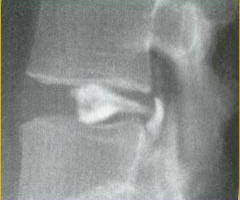

Περίπτωση: Μα. Νι. – Δισκεκτομή οσφυικής μοίρας σπονδυλικής στήλης και δυναμική σπονδυλοδεσία

Ο Μα. Νι., 30 ετών, αιτιάτο δια αριστερή όσφυοισχυαλγία η οποία συνοδευόταν από σημαντικές νευρολογικές διαταραχές στο αριστερό κάτω άκρο. Παρά την κλασσική συντηρητική αγωγή που υποβλήθηκε (φυσιοθεραπεία και φαρμακευτική αγωγή) δεν παρούσιασε σημάδια βελτίωσης κλινικά ή νευρολογικά. Εικόνα 1: Προεγχειρητικές ακτινογραφίες α. Μετωπιαία (Προσθιοπισθία) β. Οβελιαία (Πλαγία) Οσφυικής Μοίρας Σπονδυλικής Στήλης (Ο.Μ.Σ.Σ.) Παρατηρείται ύπαρξη